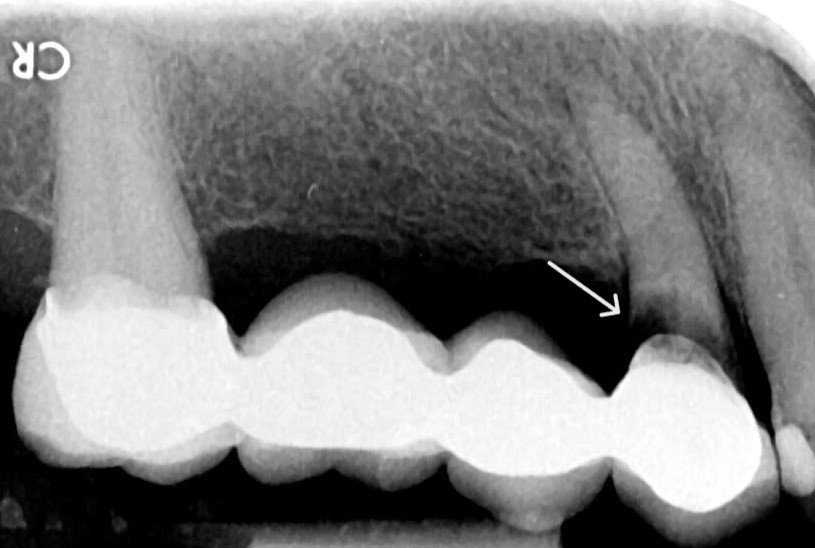

b. 치주 질환

스케일링만으로는 제거가

어려운 잇몸 아래 치석이 다량으로 쌓였을 때는

이를 통해 그 위치와 양을 정확하게

확인이 가능하며, 상담자료로 할 수 있습니다.

또한, 치조골 손실이나

잇몸(치은) 주위의 염증 상태를 관찰하여,

증세가 나타나기 전에

치주염 등 치주 질환의 진행 가능성을

예측할 수 있죠.

c. 턱뼈 및 턱관절의 상태

추가로, 이를 둘러싼 뼈의 밀도와 높이를

평가하는 데 도움을 주는데요.

이는 자연치의 안정성을 판단하고,

발치나 임플란트 시술 등의

치료 계획 수립에 중요한 근거로 사용됩니다.